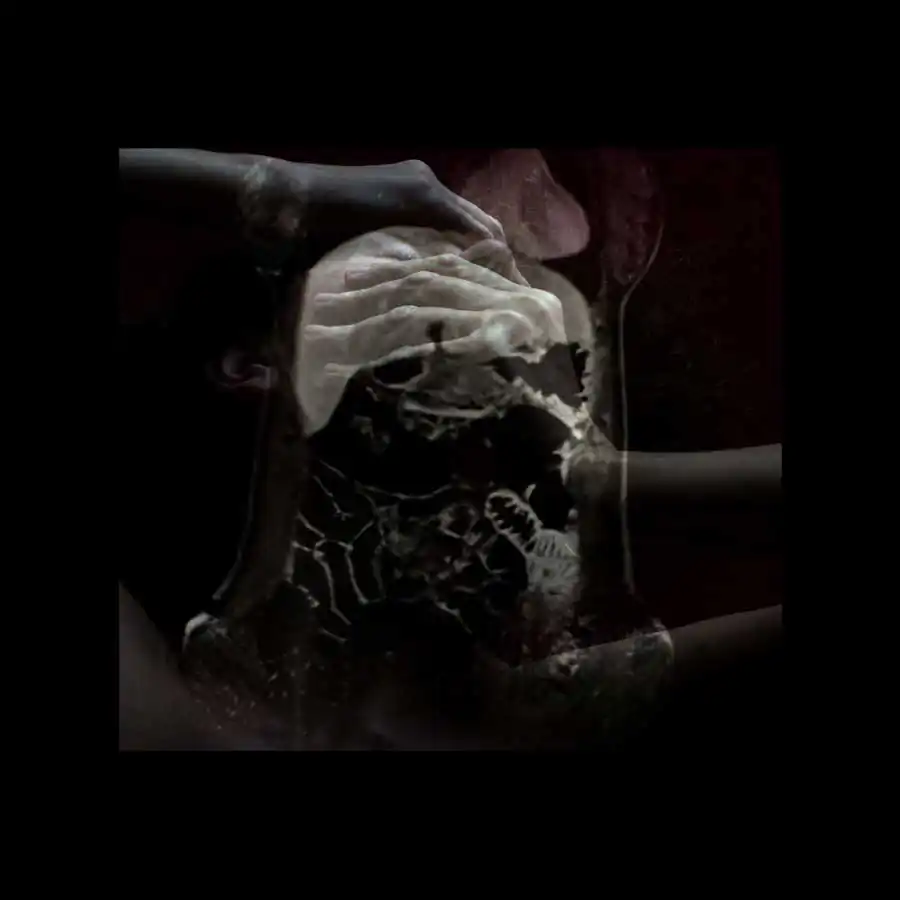

The project ‘Limits of existence’ are self-portraits compiled by the author with MRI scans. It is a case-record, in which the body appears as a subject to internal researches and the only way of communication with the outside world.

Working with the fear of physical existence termination, the author examines the physiological processes that occur during her illness with the threat of death, as the only real manifestation of life, as the limits of the possible. All thoughts, feelings and experiences, focused on physical sensations, force the author to reconsider the meaning of ‘Me’, ‘person’, ‘soul’; also the question of possibility for the spirit to overcome the boundaries of the body or expand them is raised. [Official Website]